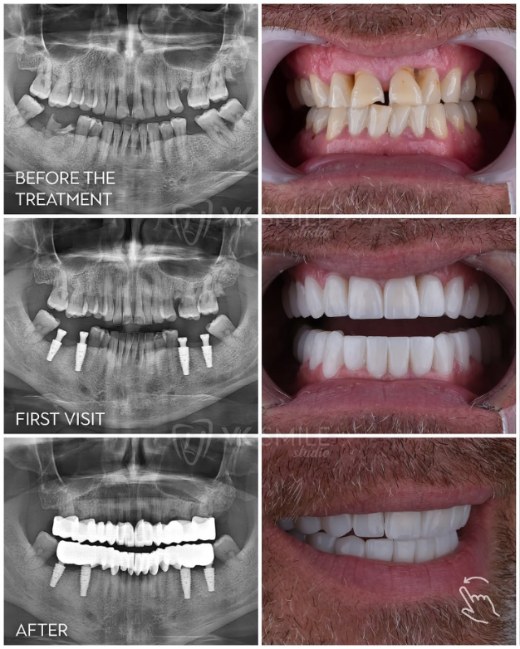

- Verified patient reviews with dated before-and-after photos.

- Clear implant brand disclosure (Straumann, Nobel, Zimmer, Megagen, etc.).